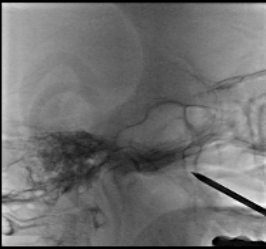

蝶腭神经节刺激